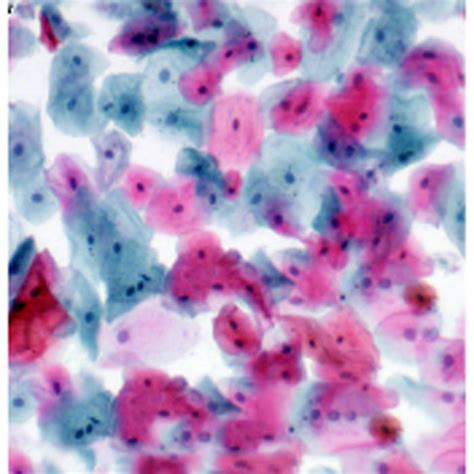

The EVG stain , or Elastic Van Gieson stain, is a staining technique used in histology to visualize elastic fibers in tissue samples. Elastic fibers are crucial components of various tissues, including blood vessels, lungs, and skin, providing them with elasticity and the ability to stretch and recoil. This staining method combines three dyes: hematoxylin, Weigert’s iron hematoxylin, picric acid, and acid fuchsin. These dyes work together to create a contrasting and easily distinguishable image of the tissue components. Elastic fibers appear black or blue-black, collagen appears red, and other tissue elements appear yellow. This differential staining allows pathologists and researchers to identify and assess the condition of elastic fibers, which is essential for diagnosing various diseases and conditions. The EVG stain is particularly valuable in identifying vascular diseases, such as atherosclerosis and aneurysms, where the integrity of elastic fibers is compromised. It is also used to evaluate lung diseases, such as emphysema, where the elastic fibers in the alveolar walls are damaged. In skin biopsies, the EVG stain can help assess the elastic fiber network, which is often affected by aging and sun damage. Overall, the EVG stain is a versatile and essential tool in histopathology, providing critical information for diagnosing and understanding a wide range of diseases and conditions affecting elastic tissues.

After this procedure, you can observe the slides under a microscope. The elastic fibers will appear black or blue-black, collagen will be red, and other tissue components will be yellow, providing a clear and informative view of the tissue structure. Accurate timing and adherence to the protocol are crucial for achieving optimal staining results.